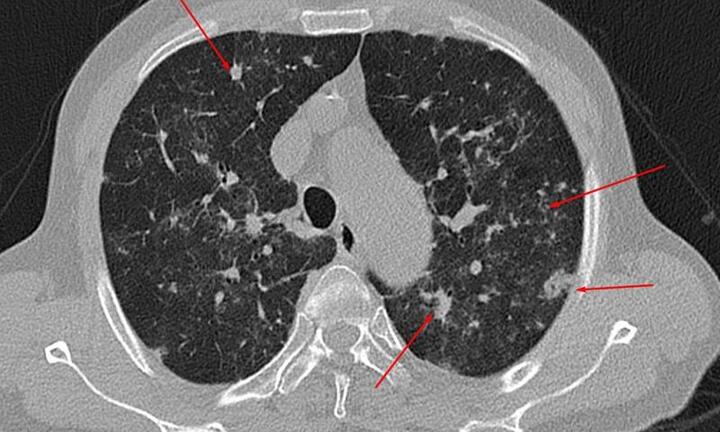

Sau khi âm tính với SARS-CoV-2, người đàn ông tiếp tục có những triệu chứng của COVID-19 và phải nhập viện điều trị.